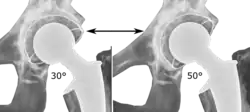

The direction of the acetabular cup influences the range of motion of the leg, and also affects the risk of dislocation.[16] For this purpose, the acetabular inclination and the acetabular anteversion are measurements of cup angulation in the coronal plane and the sagittal plane, respectively.

![Acetabular inclination is normally between 30 and 50°.[95] A larger angle increases the risk of dislocation.[16]](./_assets_/Range_of_acetabular_inclination.png)